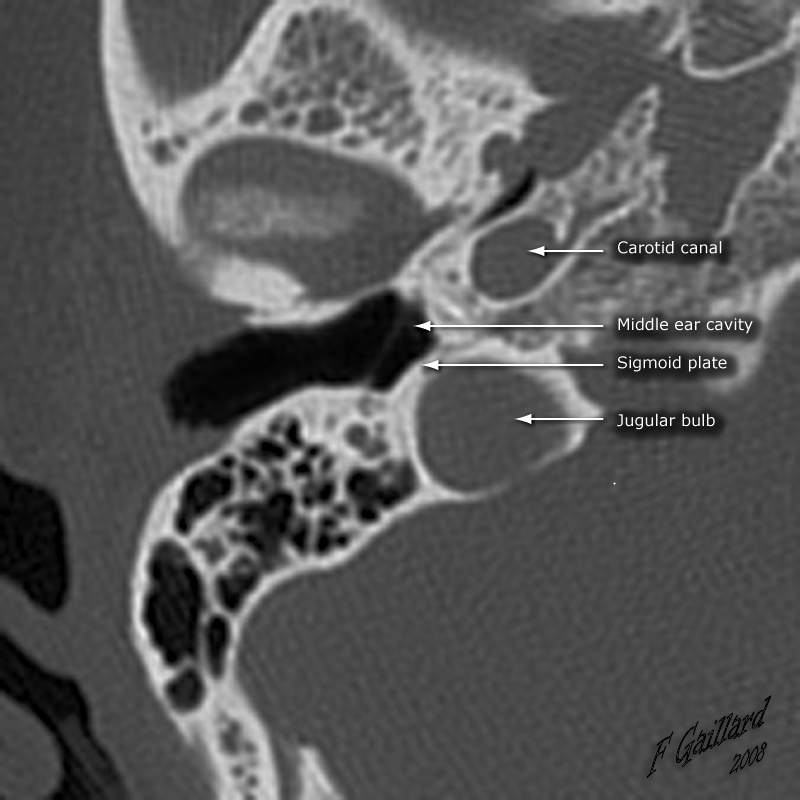

• Presents as a blue retrotympanic mass at the posterior-inferior aspect of the TM

• Basically there is a focal defect in the sigmoid plate that allows the jugular vein to push itself and get stuck in there

• Case courtesy of Frank Gaillard, Radiopaedia.org, rID: 35856